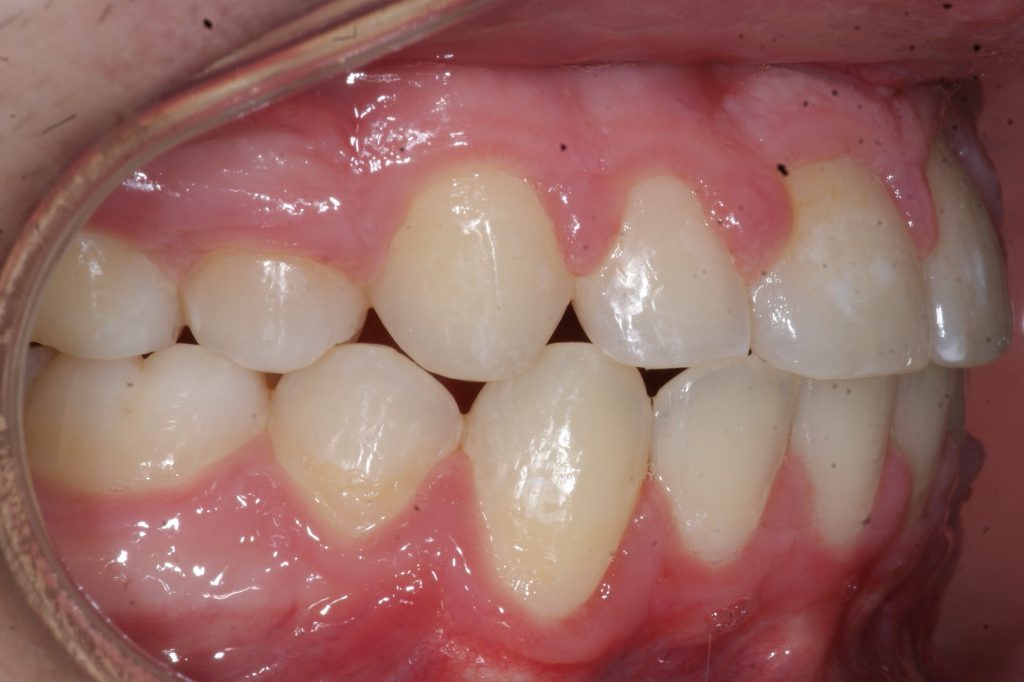

Correction d’une malocclusion de type Classe II avec chevauchement sévère aux 2 arcades. Des appareils fixes (boîtiers), une expansion palatine et l’extraction de 4 prémolaires (#14-24-35-45) furent nécessaires pour améliorer ce sourire. Traitement chez un adolescent, réalisé en 28 mois.